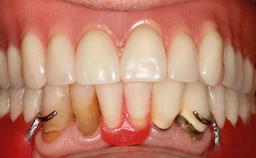

Improving an Existing Implant-supported Denture in an Alzheimer Patient with Bipolar Affective Disorder with Moderate Depression and Dementia

An 83-year-old man presented together with his caregiver at the dental department of the Medical University of Innsbruck, Austria with complaints of swelling in the right maxillary canine area and loss of retention of his 5-years-old mandibular denture. The patient had a significant medical history (20 years) of bipolar affective disorder with moderate depression (F 31.3) and dementia in Alzheimer’s disease (F 00.2). The patient had been in ambulant psychiatric therapy for his depressive illness for the past 20 years. He lived alone and had no children; his sister assisted with daily living. She reported that the patient exhibited compulsive hoarding behavior. In the previous two months, she had noted increasing disorientation and vertigo in the patient. She therefore accompanied him for a medical consultation at the Department of Psychiatry and Psychotherapy of the Medical University of Innsbruck. He was released home after a 6-week inpatient stay.

Prosthesis Type RDP

SAC Level Advanced

Defining Characteristics Fully edentulous lower jaw to be rehabilitated with an implant-borne removable overdenture